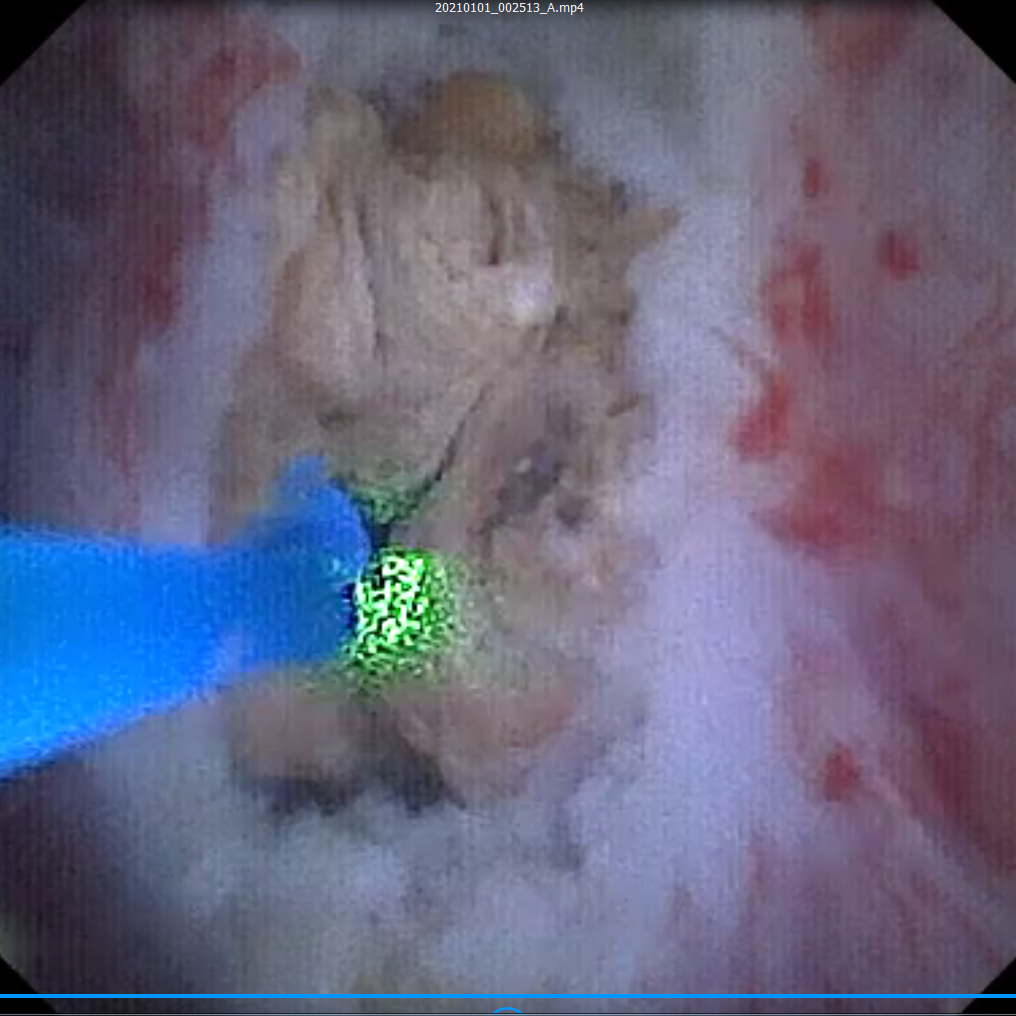

左侧输尿管结石碎石术顺利完成。术后一个月,张女士病情平稳,专家拟为其行经尿道软镜钬激光碎石取石术。虽然在术前CT中可明显看到结石,但在术中却未发现显露的结石。结石的位置一旦判断错并切开,将给患者带来严重的肾损伤。张鸿毅主任凭借多年临床经验调整镜头,看到肾下盏粘膜泛着淡黄色后确定地说到:“这里就是结石的位置!”果然,张主任用输尿管软镜钬激光将粘膜切开,大量的结石便顷刻涌出。

经过近一小时的钬激光碎石后,团队终于将结石完全击碎并取出。用同样的方法,专家团队也解决了张女士的右侧巨大肾髓质结石。术后,张女士恢复良好,已顺利出院。